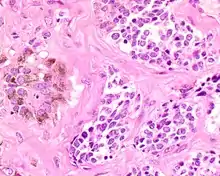

| A bone resection sample showing the pigmentation below the surface in a melanotic neuroectodermal tumor of infancy | |

The tumor is usually very well circumscribed but not encapsulated. There are two cell types present (biphasic), arranged in alveolar or tubular configurations.

There are centrally located, small, darkly staining cells comprising the majority of cells. These cells have a fibrillary cytoplasm surrounding round nuclei with coarse and heavy nuclear chromatin. These cells are surrounded by much larger polygonal cells that have open nuclear chromatin and abundant opaque cytoplasm that has granular melanin pigment.

There is usually no hemorrhage, necrosis or increased mitoses.[1][4]